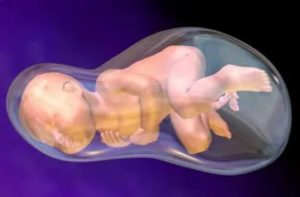

На протяжении всей беременности плод ограничен пространством матки. Помимо самого ребенка, в утробе обязательно присутствуют плацента и плодные оболочки . Данные составляющие необходимы только во время беременности и образуются уже после зачатия, поэтому после рождения ребенка они отторгаются из организма роженицы в виде последа.

Водная оболочка (или плодный пузырь) — своеобразный «мешок», в котором разивается плод, со всех сторон омываемый околоплодными водами. В большинстве случаев количество жидкости к концу срока составляет примерно 800-1500мл. Воды постоянно обновляются, полный цикл обновления — около 3 дней.

Значение околоплодных вод для ребенка неоценимо:

- Они создают необходимую и уникальную по своей структуре среду обитания для плода.

- Препятствуют сращению кожи малыша с плодным пузырем.

- Защищают малыша от травматизации.

- Помогают ребенку активно двигаться, что очень нужно для правильного развития плода.

- Защищают плаценту и сосуды пуповины от движений малыша.

- Необходимое количество вод позволяет ребенку к концу срока беременности занять правильное положение.

- Сглаживают и делают менее ощутимыми движения ребенка для мамы.

- Способствуют вместе с плодным пузырем раскрытию шейки матки при родах.